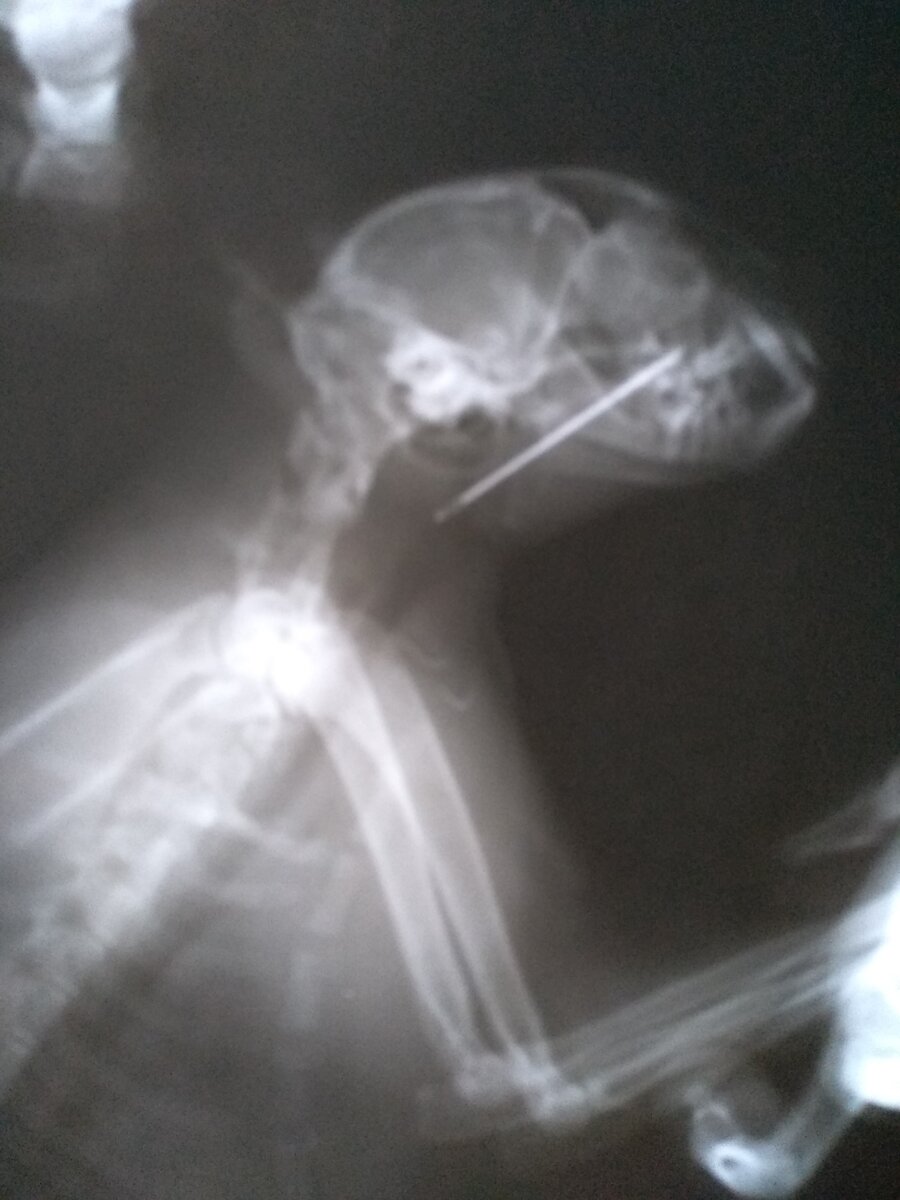

Случайно забытая на столе иголка с ниткой привлекла внимание любопытной кошки. Видимо, решив поиграть, она зацепила нитку языком и, пытаясь избавиться от неё, затянула иглу в пасть. Иголка воткнулась в верхнее нёбо остриём вперёд. Хорошо, что в это время дома находились муж с дочкой. Они сразу заметили странное поведение кошки, которую или тошнило, или она просто непрерывно чихала. При осмотре увидели нитку, торчащую изо рта. но не смогли помочь питомице, так как игла уже прочно застряла, и все попытки потянуть за нить могли только усугубить ситуацию. В ближайшей ветеринарной клинике сделали рентгеновский снимок, который вы уже видели выше. Большая игла на фоне небольшой головки нашей Лиси и сейчас выглядит устрашающе. а пять лет назад мы все всерьёз опасались за жизнь нашей любимицы. К счастью, помощь была оказана очень оперативно. Под наркозом рука опытного ветеринара моментально избавила кошку от страданий.